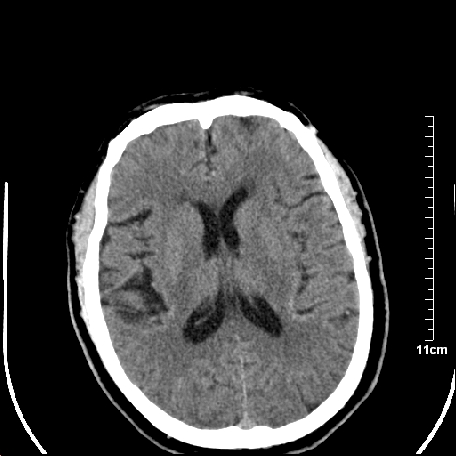

双侧外侧裂,左侧脑沟见高密度结节影,边清,还有鞍上池层面密度也高

都是血管。

脑血管硬化?高血红蛋白症?

高血红蛋白症可能

高血红蛋白症

高血红蛋白血征

1.左额叶脑软化灶。

2.老年脑,基底动脉硬化迂曲。

基底动脉硬化迂曲。高血红蛋白血症。